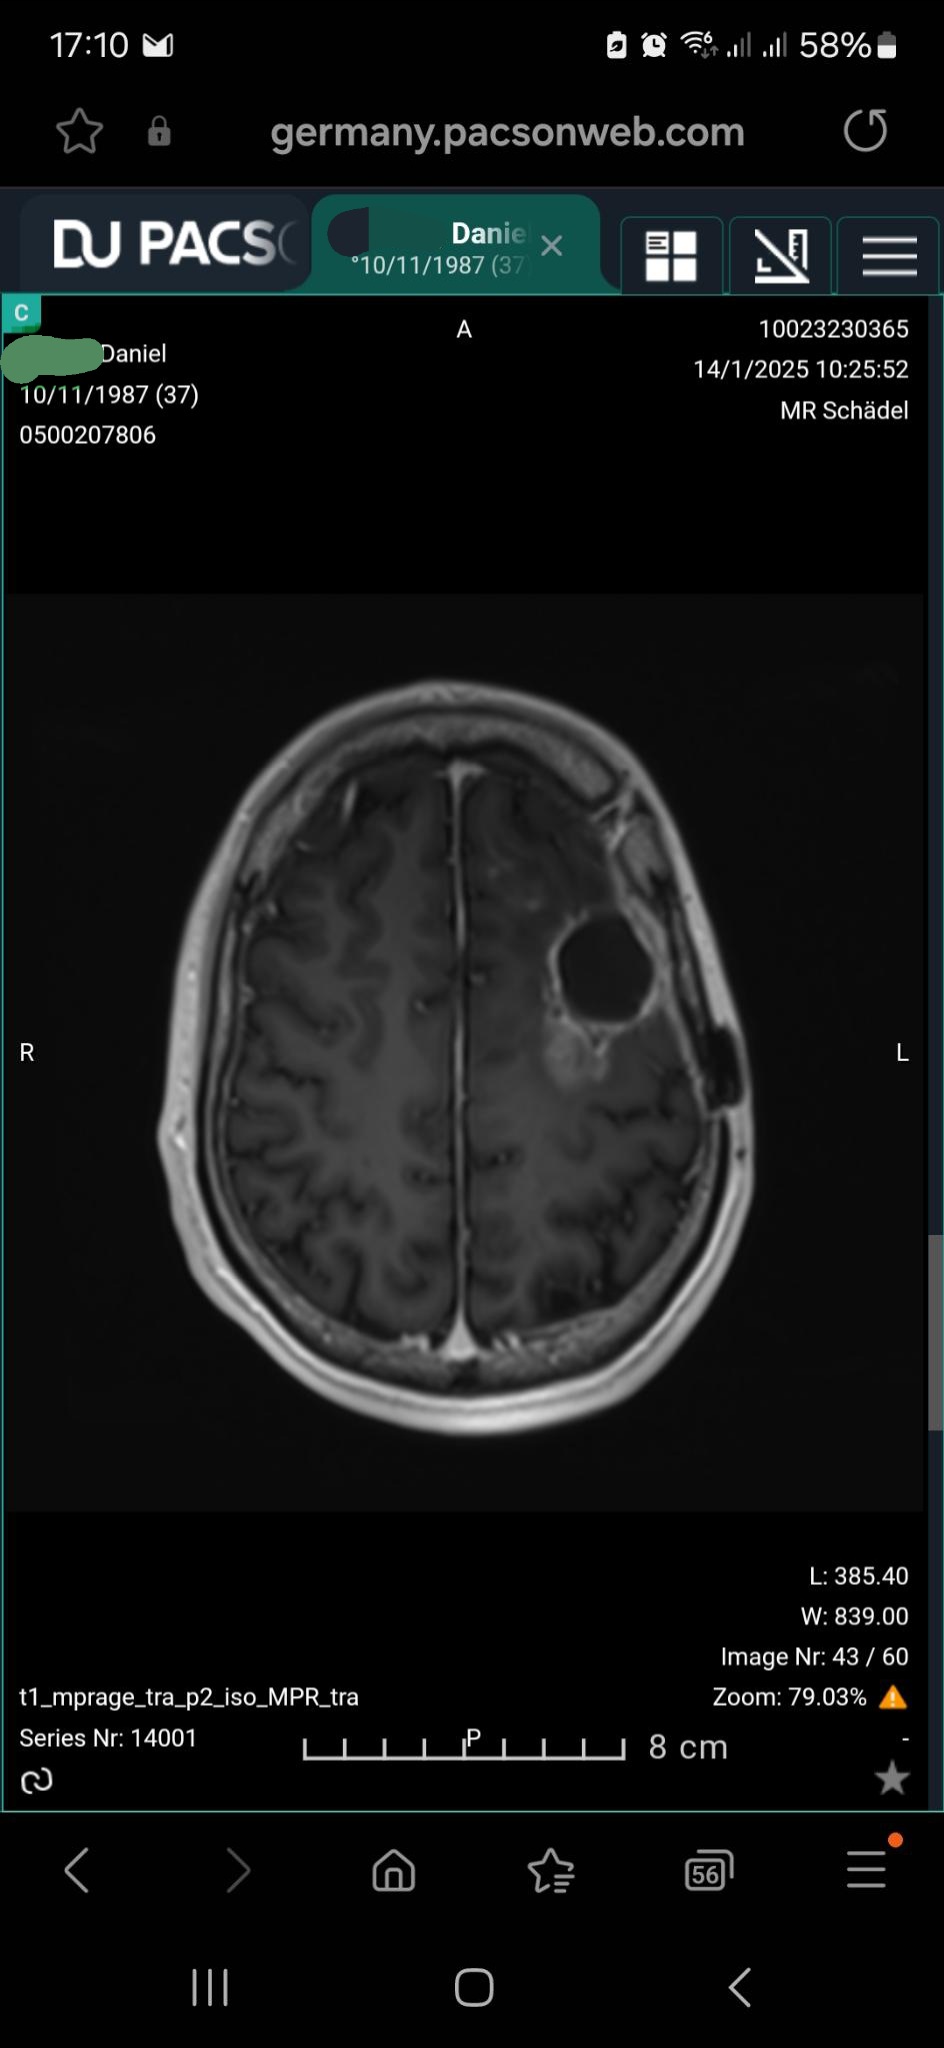

Doch 2020 änderte sich alles: Bei Dani wurde ein Glioblastom, ein als unheilbar geltender Gehirntumor, diagnostiziert. Nach einer Not-OP, Chemotherapie und Bestrahlung folgte zunächst eine positive Phase der Verlaufskontrolle bis Oktober 2024. Trotz dieser schweren Zeit hat Dani 2021–2024 sein Abitur erfolgreich nachgeholt und wollte danach Umwelt- und Energietechnik studieren – ein Ziel, das er nun erneut durchkreuzt sieht.

Im Oktober 2024 kam es leider zum Rückfall als Astrozytom, der erneut operiert werden musste, gefolgt von einer Chemotherapie bis September 2025. Seitdem leidet Dani unter ständigen Krampfanfällen, die sein Leben und das seiner Familie massiv einschränken und aktuell zunehmen.

Im Januar 2026 trat ein weiteres Rezidiv auf, das mit Bestrahlung behandelt wurde. Chemotherapie oder weitere Bestrahlungen sind leider nicht mehr möglich. Um Danis Leben zu stabilisieren, sind genehmigungspflichtige Medikamente notwendig, die jedoch extrem teuer sind.